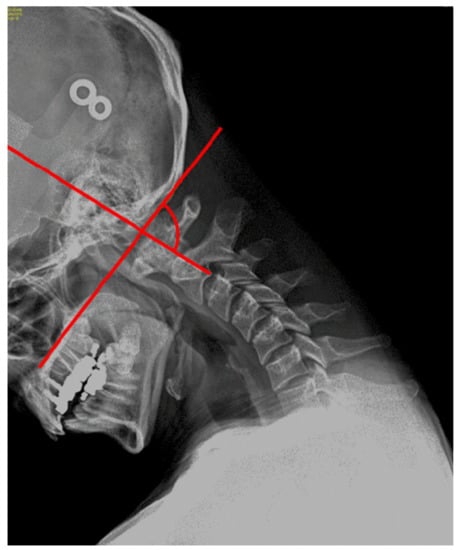

2.5. Measurement of Upper Cervical Flexion Angle Using Radiography